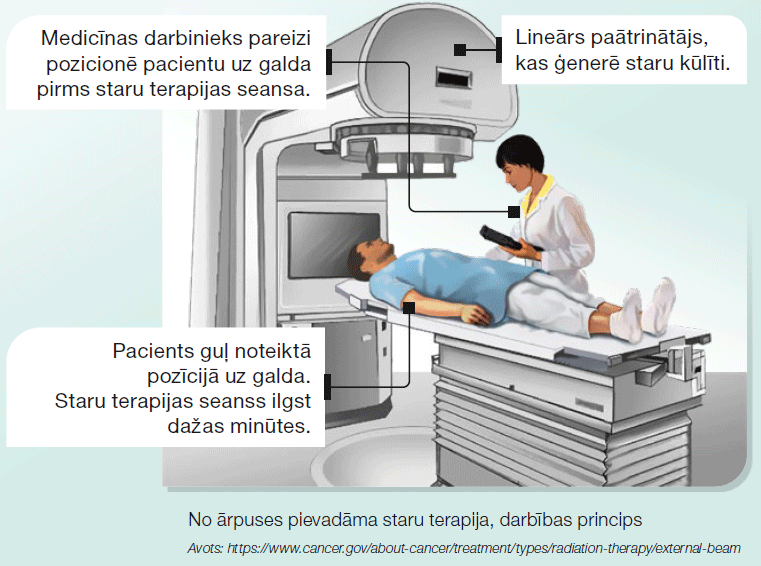

Staru terapijas pamatā ir jonizējošais starojums, ko ģenerē speciāla iekārta – lineārais paātrinātājs. Staru kūlītis tiek

ieprogrammēts trāpīt tieši ļaundabīgā audzēja šūnu sakopojumam, saudzējot blakus esošus veselus audus. Staru terapijas kurss ilgst dienas līdz nedēļas katru darba dienu. Katra staru terapijas seansa laikā tiek pievadīta neliela

starojuma deva – frakcija. Ar katru nākamo frakciju audzēja šūnās uzkrājas jonizējošā starojuma ietekme, kas izraisa vēža šūnu DNS dubultspirāles pārrāvumus un bojāeju.

Latvijā šobrīd ir četras valsts klīnikas, kur ir pieejama staru terapija – Paula Stradiņa KUS, Rīgas Austrumu KUS, Daugavpils RS, Liepājas RS. Staru terapijas pamatā ir jonizējošais starojums, ko ģenerē speciāla iekārta – lineārais paātrinātājs. Starojums tiek ieprogrammēts trāpīt tieši ļaundabīgā audzēja šūnās. Staru terapijas kurss ilgst dienas līdz nedēļas katru darba dienu. Katra staru terapijas seansa laikā tiek pievadīta neliela starojuma deva – frakcija. Ar katru nākamo frakciju audzēja šūnās uzkrājas jonizējošā starojuma ietekme, kas izraisa vēža šūnu DNS dubultspirāles pārrāvumus un bojāeju. Staru terapiju pielieto gan audzējam plaušās, gan audzēja skartiem limfmezgliem, gan plaušu vēža metastāzēm citos orgānos. Staru terapiju atsevišķos gadījumos pielieto plaušu vēža pacientiem ar mērķi novērst galvas smadzeņu metastāžu attīstību.

Plaušu vēža gadījumā visbiežāk pielieto no ārpuses pievadāmo staru terapiju (EBRT – External Beam Radiation therapy). Pacients tiek pozicionēts uz procedūru galda, un no ārpuses tiek pievadīts lineārā paātrinātāja ģenerēts staru kūlis (skat. attēlu). Pēc iespējas staru terapiju sinhronizē ar pacienta elpošanas kustībām. Ieelpas un izelpas laikā ar speciālo ierīci tiek piefiksētas krūškurvja kustības, staru kūlīša pievade tiek koriģēta, lai trāpītu precīzi audzēja šūnām bez elpošanas kustību radītas nobīdes.

Plaušu vēža gadījumā visbiežāk pielieto no ārpuses pievadāmo staru terapiju (EBRT – External Beam Radiation therapy). Pacients tiek pozicionēts uz procedūru galda, un no ārpuses tiek pievadīts lineārā paātrinātāja ģenerēts staru kūlis (skat. attēlu). Pēc iespējas staru terapiju sinhronizē ar pacienta elpošanas kustībām. Ieelpas un izelpas laikā ar speciālo ierīci tiek piefiksētas krūškurvja kustības, staru kūlīša pievade tiek koriģēta, lai trāpītu precīzi audzēja šūnām bez elpošanas kustību radītas nobīdes.